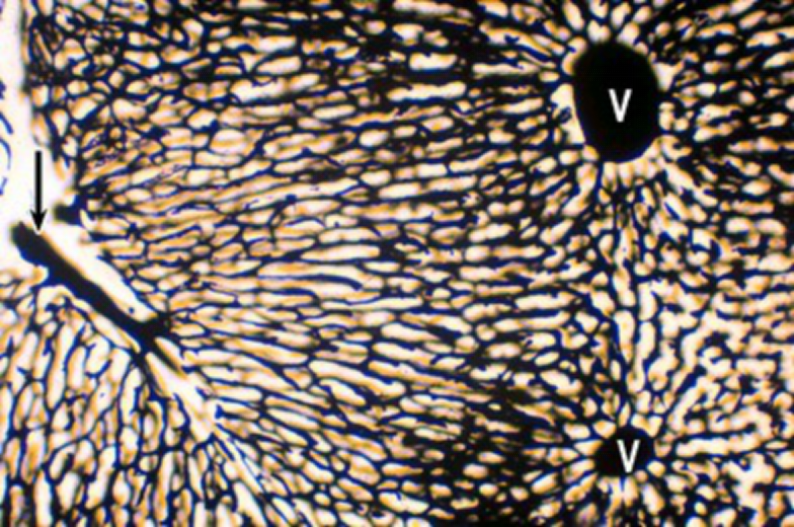

肝血管(兔肝 门静脉墨汁灌注):

肝血液通路(从肝小叶周边流向中央):

门静脉→→小叶间静脉

肝动脉→→小叶间动脉

↓ ↓

中央静脉←肝血窦

↓

肝静脉←小叶下静脉